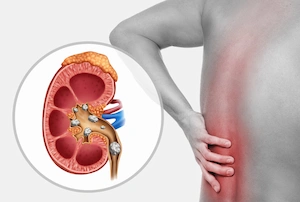

لگنچه کلیه (Renal Pelvis) در واقع بخش مرکزی و قیف مانند کلیه است که ادرار در آن جمع شده و سپس به سمت لوله های حالب هدایت می شود. تشکیل سنگ لگنچه کلیه می تواند باعث انسداد مسیر ادرار و بروز دردهای شدید کلیوی شود. علائم سنگ لگنچه کلیه معمولاً شامل درد مبهم یا شدید در پهلو، تهوع و گاهی مشاهده خون در ادرار است.

اهمیت درمان سریع این سنگ ها در این است که ماندگاری طولانی مدت آن ها در لگنچه می تواند به بافت کلیه آسیب زده و عملکرد آن را مختل کند. در کلینیک سنگ شکنی دکتر اصغر فرهادی، هدف اصلی ما دفع سنگ لگنچه کلیه بدون جراحی و بیهوشی و بستری و درد و با کمترین میزان استرس برای بیمار است.

سنگ لگنچه کلیه به رسوبات سختی گفته می شود که در بخش مرکزی کلیه (لگنچه) تشکیل شده و مانع از جریان طبیعی ادرار می شود.